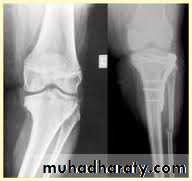

Tibial plateau fractures:Direct blow or fall from height may cause fracture of one tibial condyle or both.

Fracture lateral condyle is the commonest named as bumper fracture

caused by a force that abducts the tibia upon femur while the foot is fixed on ground.Patient usually is an adult, the knee joint is swollen, bruises, there is diffuse tenderness and doughy feel of haemarthrosis.

Imaging : X-ray

: anteroposterior, lateral & oblique views.

CT -Scan may used to detect amount of depression and comminuation.Tibial plateau fracture